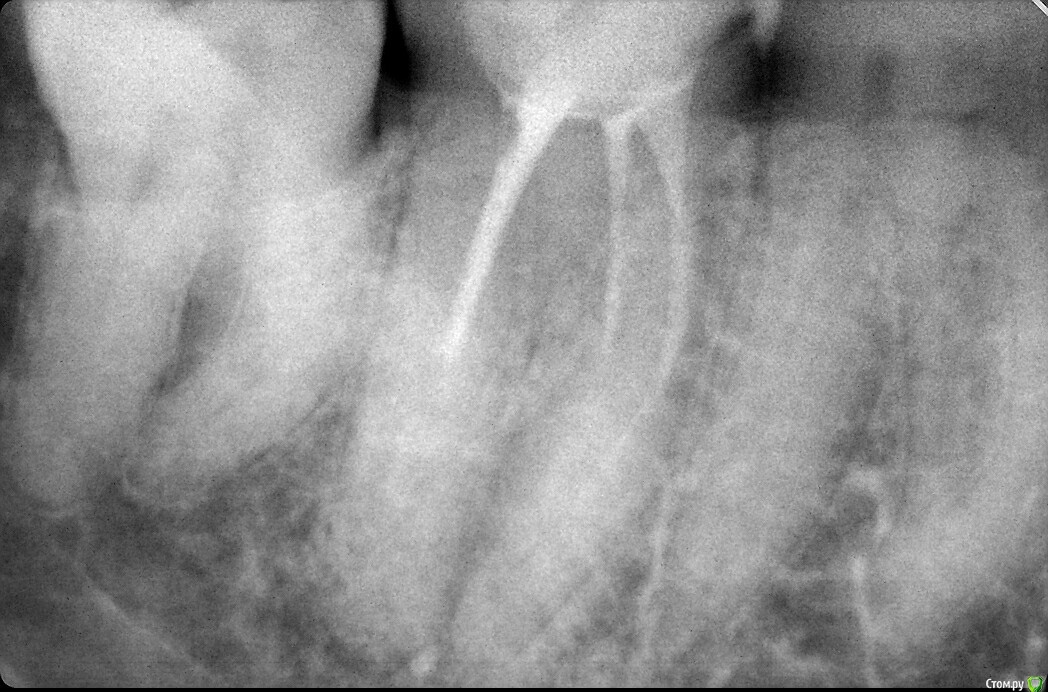

Antanta Опубликовано 25 ноября, 2018 Поделиться Опубликовано 25 ноября, 2018 Добрый вечер. Сделала огромную ошибку. Такие длинные корни и такой короткий штифт в дистальном канале получился. Вкладка сделана непрямым методом. С техником решили не делать штифты в медиальные каналы, пришлось заполнить цементом. Зуб сейчас под временной коронкой, планируется в ближайшее время изготовить металлокерамическую коронку. Но я мучаюсь и не могу решить, выпилить и переделать вкладку, сделать в дистальном канале штифт длиннее. Или оставить как есть, запротезировать и ждать..будет ли перелом дистального корня? Феррул у зуба есть, была своя щечная стенка, остальная часть зуба была восстановлена композитом, язычная стенка разрушена до десны, медиальная и дистальная чуть выше десны. Пожалуйста, помогите советом Ссылка на комментарий

Doc Опубликовано 26 ноября, 2018 Поделиться Опубликовано 26 ноября, 2018 Добрый вечер. Сделала огромную ошибку. Такие длинные корни и такой короткий штифт в дистальном канале получился. Вкладка сделана непрямым методом. С техником решили не делать штифты в медиальные каналы, пришлось заполнить цементом. Зуб сейчас под временной коронкой, планируется в ближайшее время изготовить металлокерамическую коронку. Но я мучаюсь и не могу решить, выпилить и переделать вкладку, сделать в дистальном канале штифт длиннее. Или оставить как есть, запротезировать и ждать..будет ли перелом дистального корня? Феррул у зуба есть, была своя щечная стенка, остальная часть зуба была восстановлена композитом, язычная стенка разрушена до десны, медиальная и дистальная чуть выше десны. Пожалуйста, помогите советомНу, конечно же дистальный мог быть в два раза длиннее, а медиальные легко могли быть длиной с дистальную ножку, какая она есть сейчас. Но выпиливать из-за этого вкладку уж точно нет смысла. Вреда можете нанести больше, чем если так оставить. При наличии нормального ферула и качественного прилегания коронки оно еще сто лет простоит! Начнете выпиливать, так может и треснуть, и перегреться, и лишних тканей спилите. Так что не заморачивайтесь, так сойдет. На будущее просто учтите. 4 Ссылка на комментарий